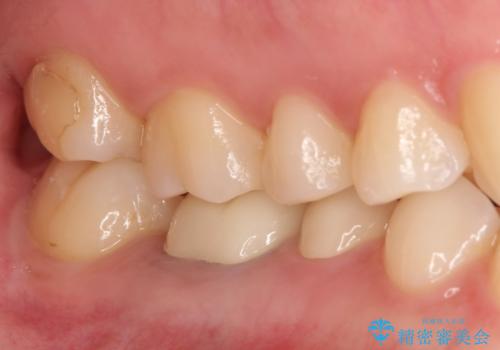

【メタルフリー】銀歯を白くしたい。オールセラミッククラウン。

- 銀歯を白くしたいと希望され来院されました。

すぐにでも白くしたいとのことで、2回目の来院で銀歯を白い仮歯に変更し喜んでいただきました。

ただ単純に白くするでけではなく拡大鏡を使用し、丁寧な処置を行なっております。